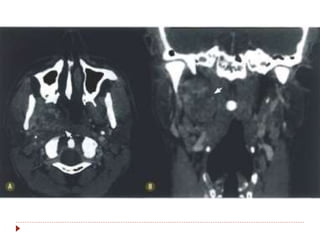

 TC contrastada é o método de escolha (1-3 mm).

 RM  T1, T2, STIR, gadolíneo, supressão de

gordura, difusão.

Nasofaringe  TC contrastadaé o método de escolha (1-3 mm).  RM  T1, T2, STIR, gadolíneo, supressão de gordura, difusão.